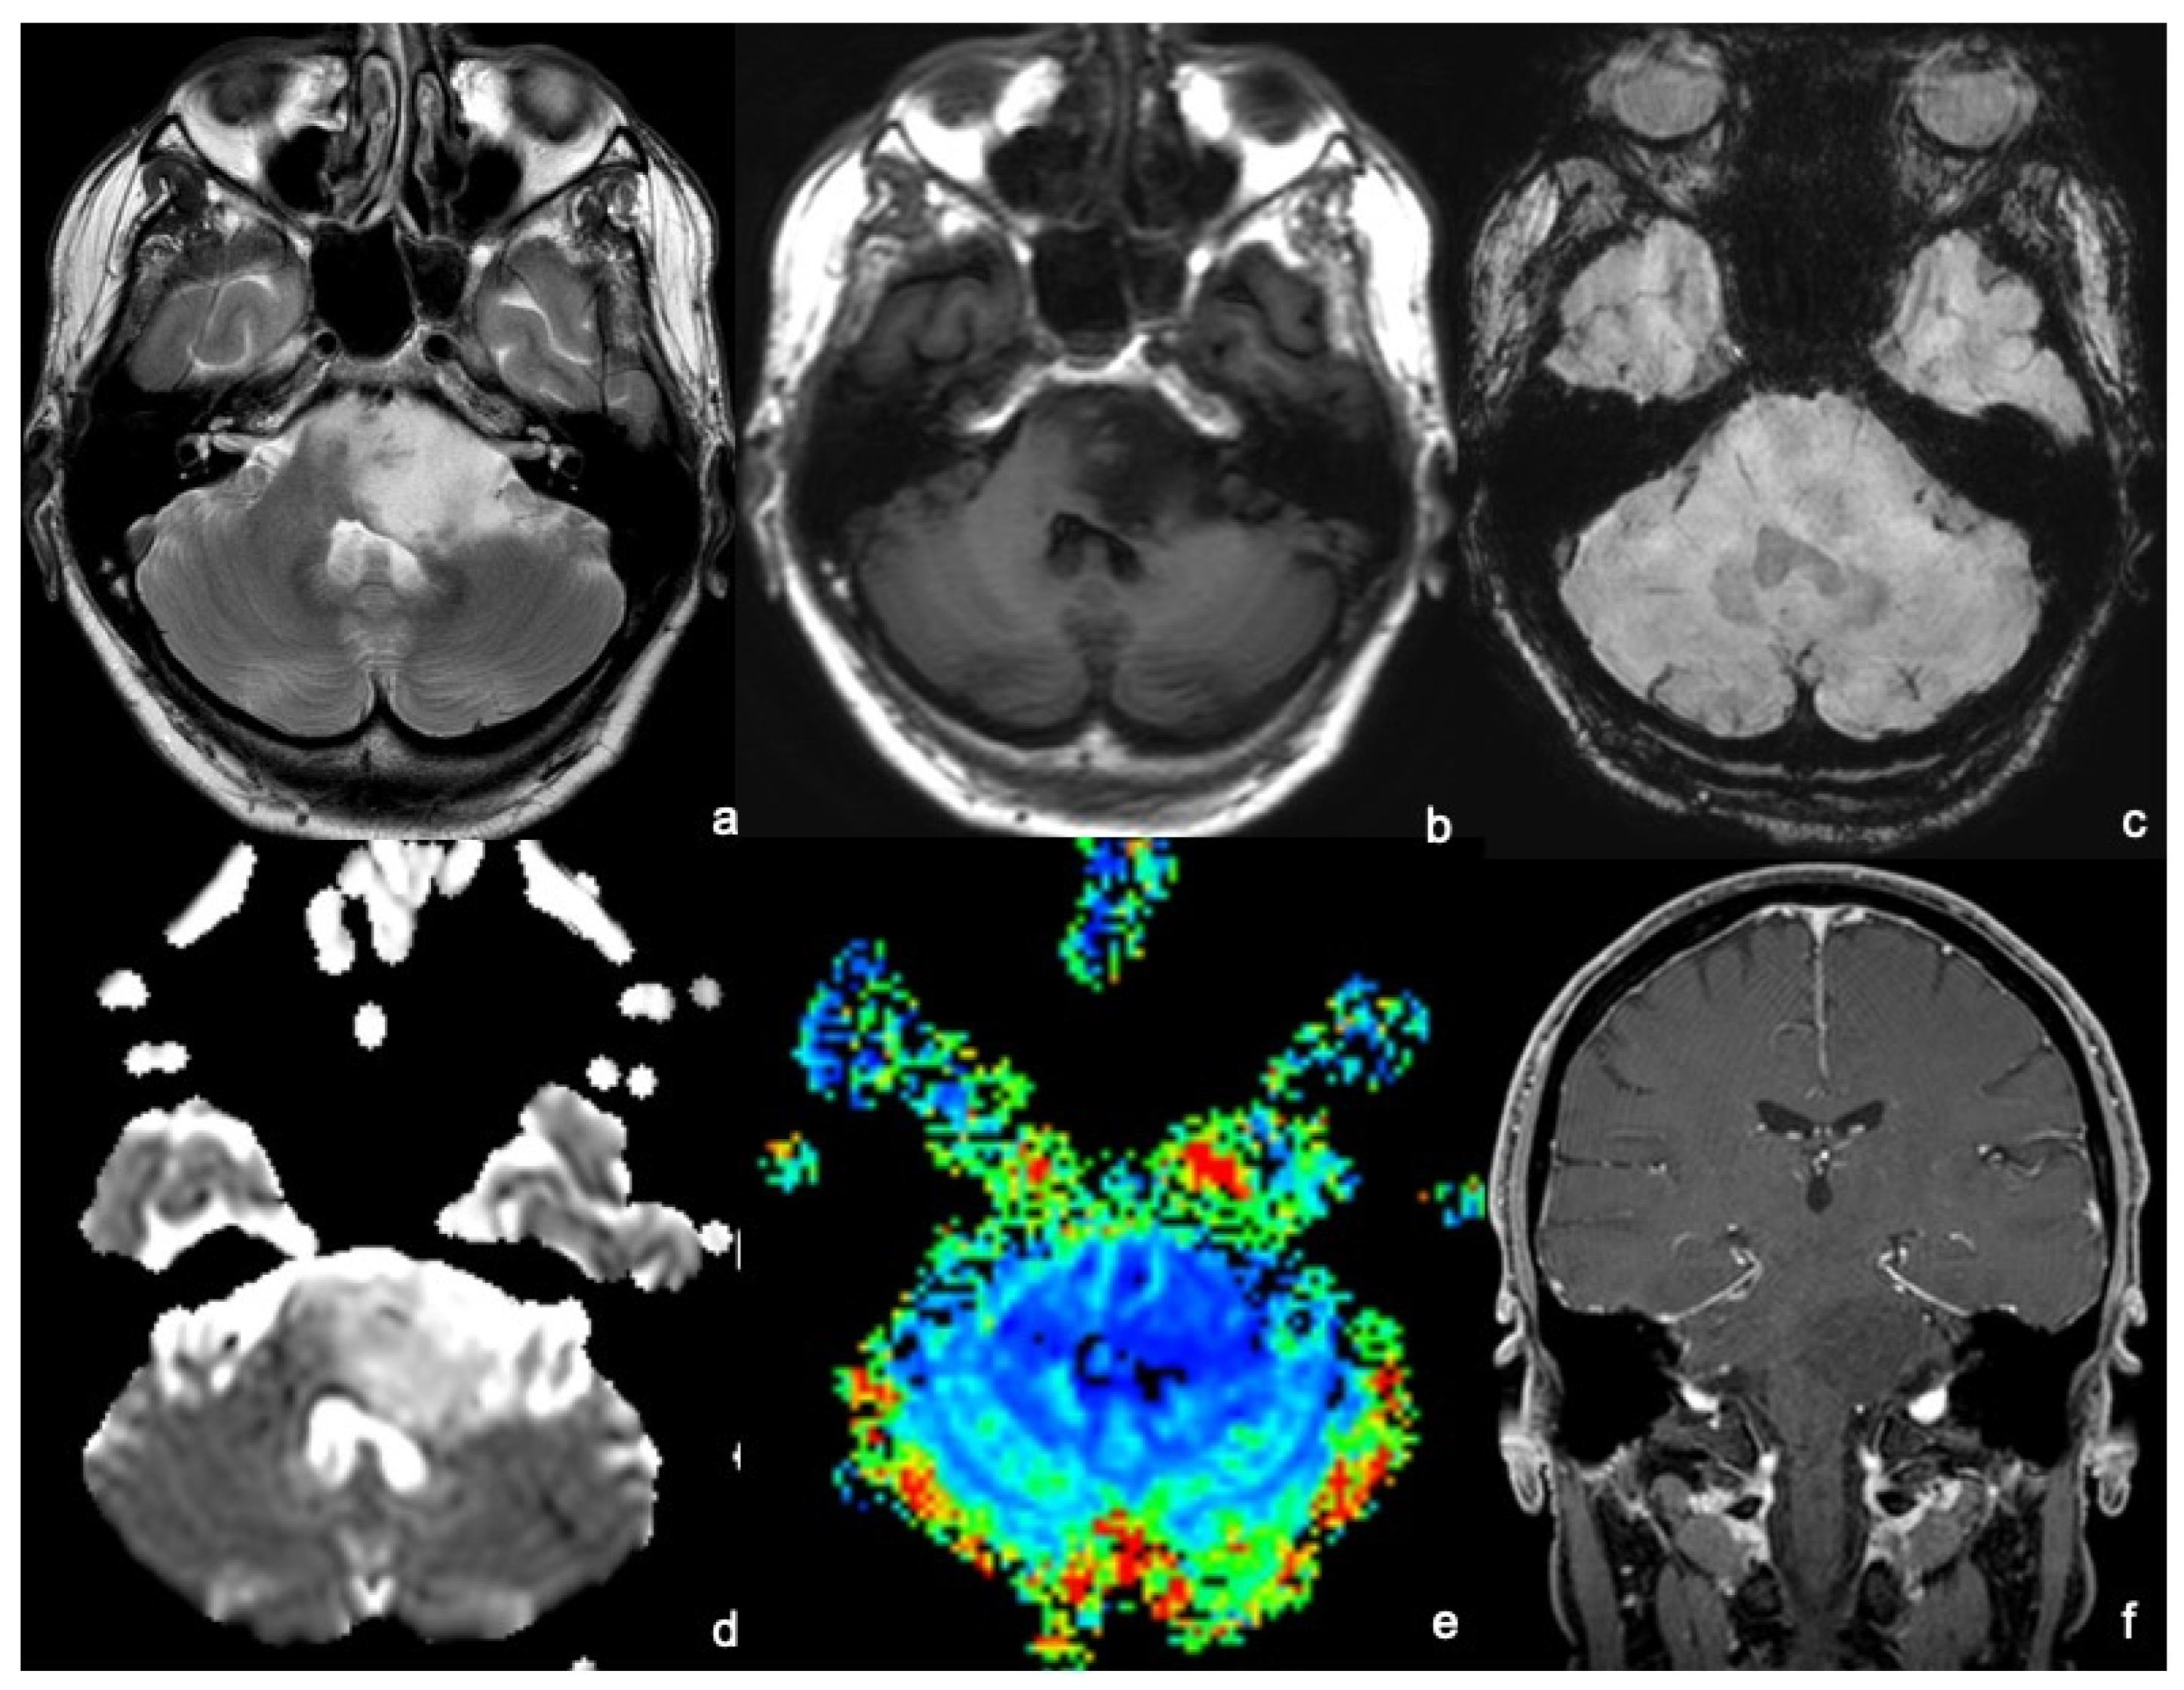

Specific brain MRI findings of 8 patients Download Scientific Diagram What Is A Mri In Psychology Magnetic resonance imaging (mri) uses changes in electrically charged molecules in a magnetic field to form images of the brain. Neuroimaging, or brain scanning, produces images of the brain or other parts of the nervous system. What is an mri study in psychology? In psychology, two main types of mri scans are used: Current neuroimaging techniques typically show the brain’s.. What Is A Mri In Psychology.